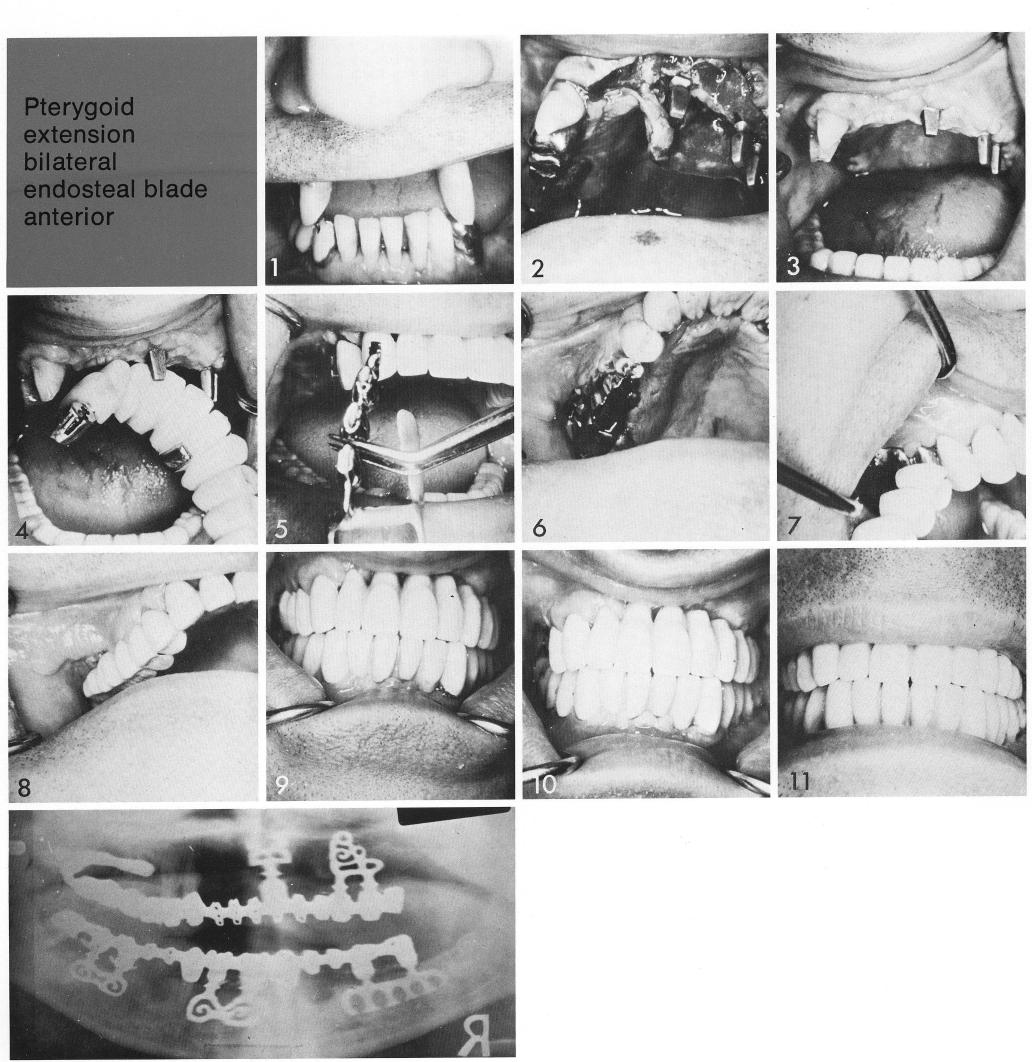

Pterygoid extension bilateral

endosteal blade

anterior

The patient had a very unattractive maxillary situation (1). When the left cuspid was extracted, a bladevent was inserted between the midline and the socket (2). A double-posted, sinus-accommodating bladevent was inserted behind the socket (2). When the tissues adequately healed (3), impressions were taken for a right unilateral pterygoid extension implant to join with a three-quarter arch restoration. The restoration had a cantilevered female attachment (4) for anchoring the male attachment incorporated in the pterygoid extension implant (5). The pterygoid extension implant was inserted (6). After the tissues healed over the pterygoid extension implant, the remaining portion of the restoration was finished (7), and the occlusion carefully checked (8-10).